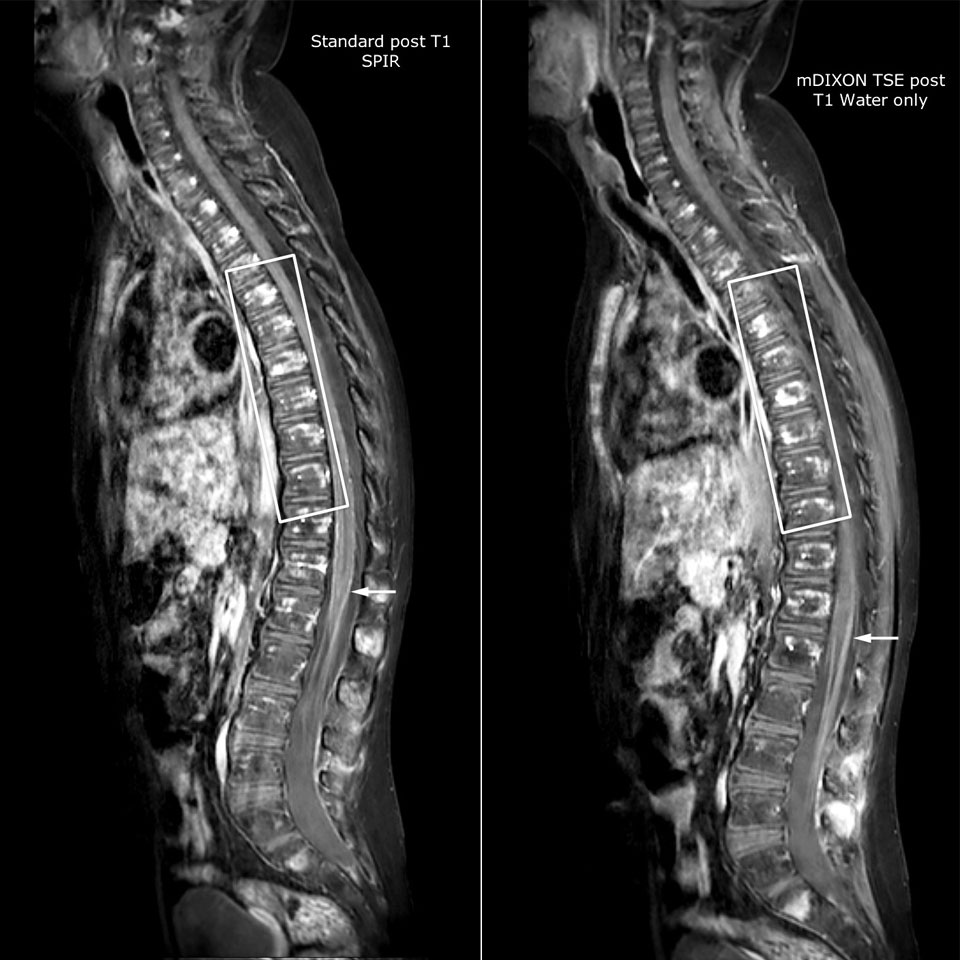

Routinely obtaining homogeneous fat suppression under virtually all conditions with mDIXON TSE

Philips mDIXON TSE is a two-point DIXON technique that separates water and fat signals, for time-efficient fat-free imaging, even in challenging neuro anatomy.

“mDIXON TSE has been one of the most significant improvements in imaging sequences that we have utilized to date at PCH,” says Dr. Miller. “Its multi-parametric acquisition allows us to obtain fat suppressed images and equivalent non-fat suppressed T2 images all in the same sequence. In addition, prior methods of fat suppression could be artifactually corrupted by poor patient anatomy or poor operator application, but with mDIXON we now have a robust and reliable method of fat suppression.”

Fat saturation is historically challenging at the ends of fields of view, especially in total spine imaging and in difficult patient anatomy such as the lower regions of the neck. “Due to the unique fat suppression capabilities of mDIXON, however, these challenges no long apply,” says Dr. Miller. “We routinely obtain homogeneous fat suppression under virtually all conditions. It has also led to some efficiencies by not having to repeat sequences because of that technical failure.”

mDIXON TSE makes a difference

“mDIXON TSE is most useful in patients with lesions or abnormalities in the soft tissues such as the face and neck, and for patients with contrast enhancing abnormalities that are mostly visible with fat suppression,” says Dr. Miller. “All our spine imaging now routinely contains mDIXON water-only T2 images, and this allows us to identify pathology that may be obscured by non-fat suppressed imaging such as injuries of the bone. And it’s not necessary to obtain additional standard TSE T2 images because the in-phase mDIXON images are equivalent to standard TSE T2 images.”

“mDIXON TSE has increased our diagnostic confidence in ruling in or ruling out abnormalities in which fat suppression is critical to diagnosis, such as metastatic disease or osseous abnormalities.”

Miller JH, Pokorney A, Naidu P, Eggers H, Shar M, Perkins T. Improved Fat Suppression and Field Homogeneity of mDixon TSE Total Spine Imaging compared to SPIR Fat Saturation for Post-Contrast T1-weighted Imaging. Proceedings of the Joint Annual Meeting of the ISMRM-ESMRB. Milan, Italy: International Society for Magnetic Resonance in Medicine, 2014.